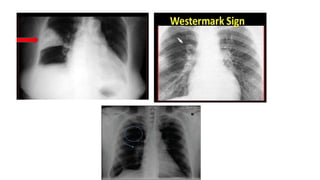

Chest X ray

• Most patients with pulmonary embolism have abnormal but nonspecific

chest radiographic findings.

• Common radiographic findings include atelectasis, pleural effusion,

pulmonary infiltrates, and mild elevation of a hemidiaphragm.

• Classic findings of pulmonary infarction—such as Hampton’s hump or

decreased vascularity (Westermark’s sign)—are suggestive but infrequent.

• Hampton hump refers to a dome-shaped, pleurally-based opacification in

the lung.

• Pala sign is a prominent pulmonary artery that can be caused either

by pulmonary hypertension that develops or by distension of the vessel by

a large pulmonary embolus.

• Westermark’s sign – peripheral oligemia.

• A normal chest radiograph in a patient with otherwise unexplained acute

dyspnea or hypoxemia is strongly suggestive of embolism.